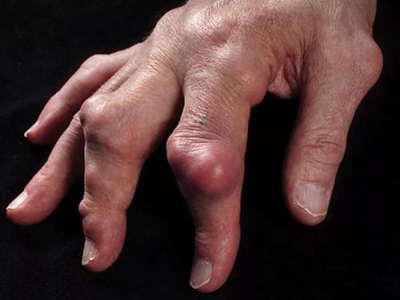

痛风病程较长,常反复发作而迁延不愈形成痛风石,是痛风的特征性临床表现,常见于指关节、第一跖趾关节、耳廓等处。外观为隆起、大小不一的不规则的黄白色赘生物,表面菲薄,破溃后排出白色粉状或糊状尿酸盐结晶物,经久不愈,但较少继发感染。部分患者伴有肾结石及肾脏病变。